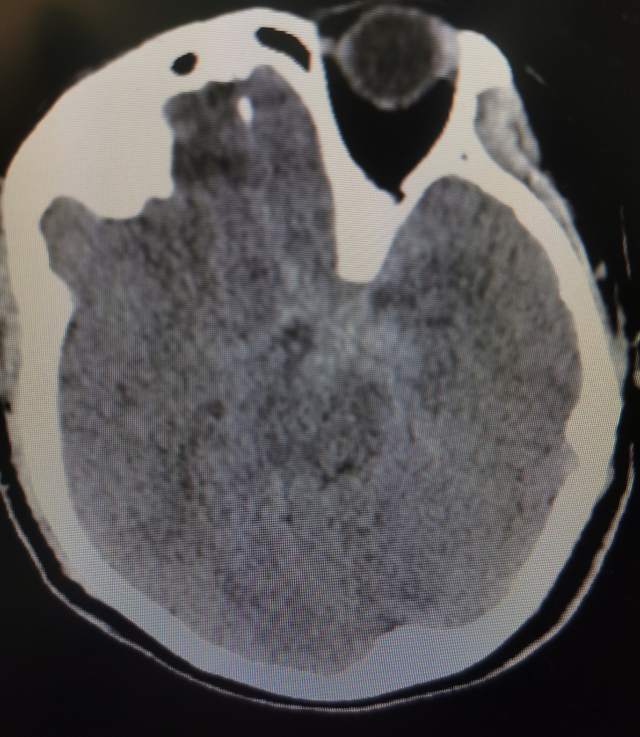

午夜,54岁中年女性,颅内多发动脉瘤破裂出血 ,一个左侧A1动脉瘤,一个左侧胚胎型大脑后动脉瘤(责任动脉瘤;起始部和远端上壁各见一个小泡,后面这个为破裂点;起始部累及粗大胚胎型大脑后动脉),